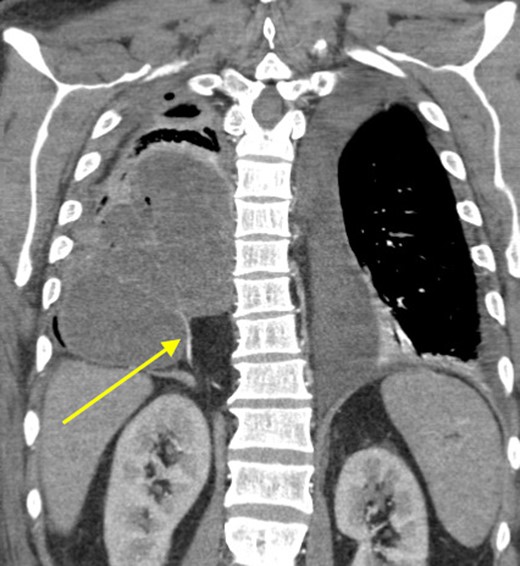

Coronal view showing persistent empyema and anomalous arterial supply into sequestration.

At that time, we started to wonder if this patient had ILPS, which prompted us to scrutinize his prior CT scans. Surprisingly, we noticed an anomalous arterial supply from the right renal artery that traversed through his Bochdalek hernia and into the sequestration (Figs 2 and 3). Two days after the operation, the patient was extubated and his clinical course was relatively benign. Also, no pathogens were detected by microbiological analysis of the intraoperative cultures and bronchial lavage. Pleual biopsies from the first operation just showed some acute fibrinous pleuritis with calcium. One week later, his mental status recovered at baseline, he was breathing without supplemental oxygen and his WBCs count had normalized. The patient was discharged to rehab with follow up in the clinic to discuss surgical resection of the ILPS in order to prevent recurrent symptoms.